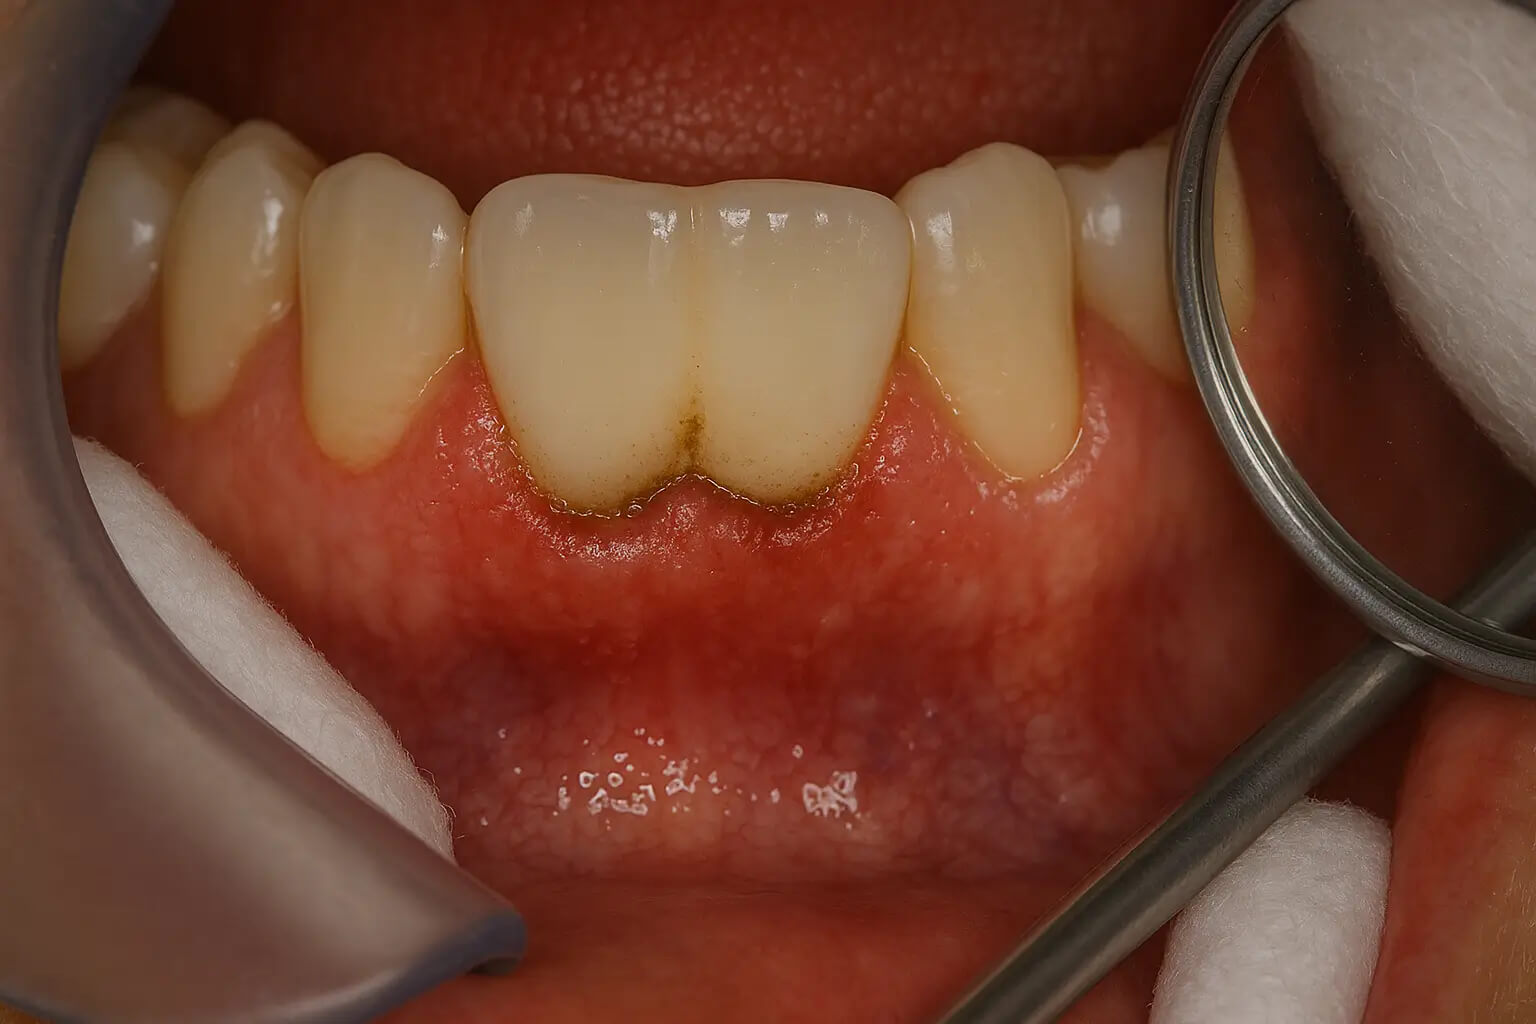

1. عفونت و التهاب لثه

عفونت و التهاب لثه یکی از شایعترین عوارض پس از کاشت ایمپلنت است و معمولاً در روزها یا هفتههای ابتدایی بعد از جراحی بروز میکند. این وضعیت زمانی رخ میدهد که باکتریها در اطراف پایهی ایمپلنت تجمع پیدا کنند و موجب تحریک یا التهاب بافت لثه شوند. علائمی مانند قرمزی، تورم، احساس درد، بوی بد دهان یا حتی ترشح چرک از محل جراحی میتواند نشانهی بروز عفونت باشد. در برخی موارد، اگر درمان به موقع انجام نشود، التهاب ممکن است به استخوان فک گسترش یابد و حتی باعث شل شدن یا شکست ایمپلنت دندان شود.

مهمترین علت بروز عفونت، رعایت نکردن بهداشت دهان و دندان پس از کاشت ایمپلنت است. باقی ماندن ذرات غذا بین ایمپلنت و لثه محیطی مناسب برای رشد باکتریها فراهم میکند. همچنین عواملی مانند مصرف سیگار، ضعف سیستم ایمنی بدن، یا استفاده نادرست از آنتیبیوتیکها میتواند احتمال التهاب و عفونت را افزایش دهد. برای جلوگیری از این مشکل، باید طبق توصیهی دندانپزشک، از مسواک نرم، نخ دندان مخصوص ایمپلنت و دهانشویه آنتیباکتریال استفاده کرد.

یکی از مراقبتهای مهم بعد از ایمپلنت، جرم گیری ایمپلنت دندان است. تجمع پلاک و جرم روی ایمپلنت میتواند منجر به التهاب لثه و تحلیل استخوان شود. برای جلوگیری از این مشکلات، به طور منظم به دندانپزشک مراجعه کرده و از ابزارهای مخصوص برای تمیز کردن ایمپلنت استفاده کنید.